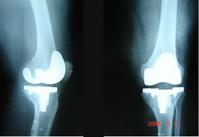

治疗

根据疾病种类不同及病情发展程度不同,关节炎的治疗包括药物治疗、辅助治疗和手术治疗。手术治疗,对于疾病已经发展到晚期的病人,不失为一种好的治疗手段;对于早中期的病人,一般采取药物治疗并配合其他方法辅助治疗。要积极采取正确、有效的手段,尽早治疗疾病,尽早控制病情。由于关节炎是一个很广泛的概念,在没有具体到时哪一种关节炎之前,不能做出具体的治疗方法,所以,具体治疗请阅读每一种关节炎其本身词条。